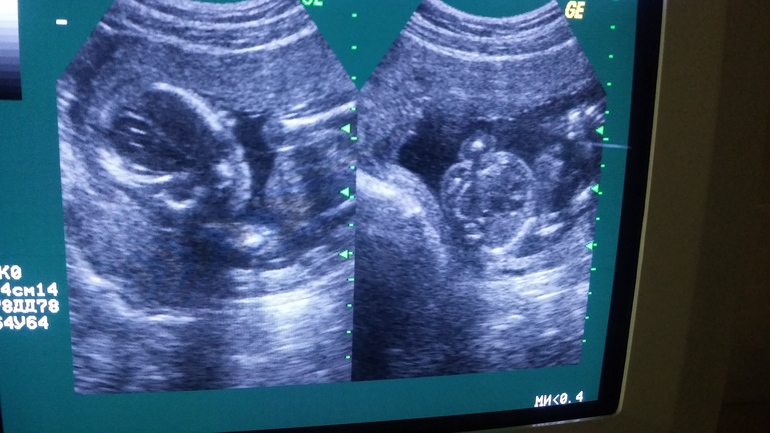

Встали в 7 утра всей семьей, сына увезли к сестре и с мужем поехали в клинику на УЗИ, что бы узнать пол нашей крохи. Записаны были за неделю, приезжаем, на ресепшене нас встречает милая девушка и провожает в кабинет, врача нет, ждем....Через пару минут меня просят пройти в соседний кабинет, к врачу. Захожу, за столом сидит отвратительного вида тетка, и так с укором и наездом заявляет " Я вобще то пол не определяю, вот поедите вы на 20 неделе на бесплатный скрининг там вам возможно скажут пол!" Я потеряла на секунду дар речи, потом говорю вы мне с какой целью это говорите, я записалась в вашу частную клинику, готова отвалить вам денег, а вы мне про скрининг лекции читаете?!!!!! Сказать что я была в ярости, ничего не сказать. Вылетела пулей из этой шараги, муж следом, сели в машину я начала судорожно обзванивать клиники, естественно запись везде максимум на следующий день, а я хочу сегодня, сейчас, я пол ночи уснуть не могла в предвкушении, а тут такое свинство..... разревелась. С 10 попытки нашли клинику, где меня были готовы принять СЕЙЧАС!!!!

И тадам!!!!! У нас будет доченька, Сонечка, такая желанная и долгожданная!!!! Мы так рады, просто слов нет, теперь я довольна, как слон и люблю весь мир!!!!